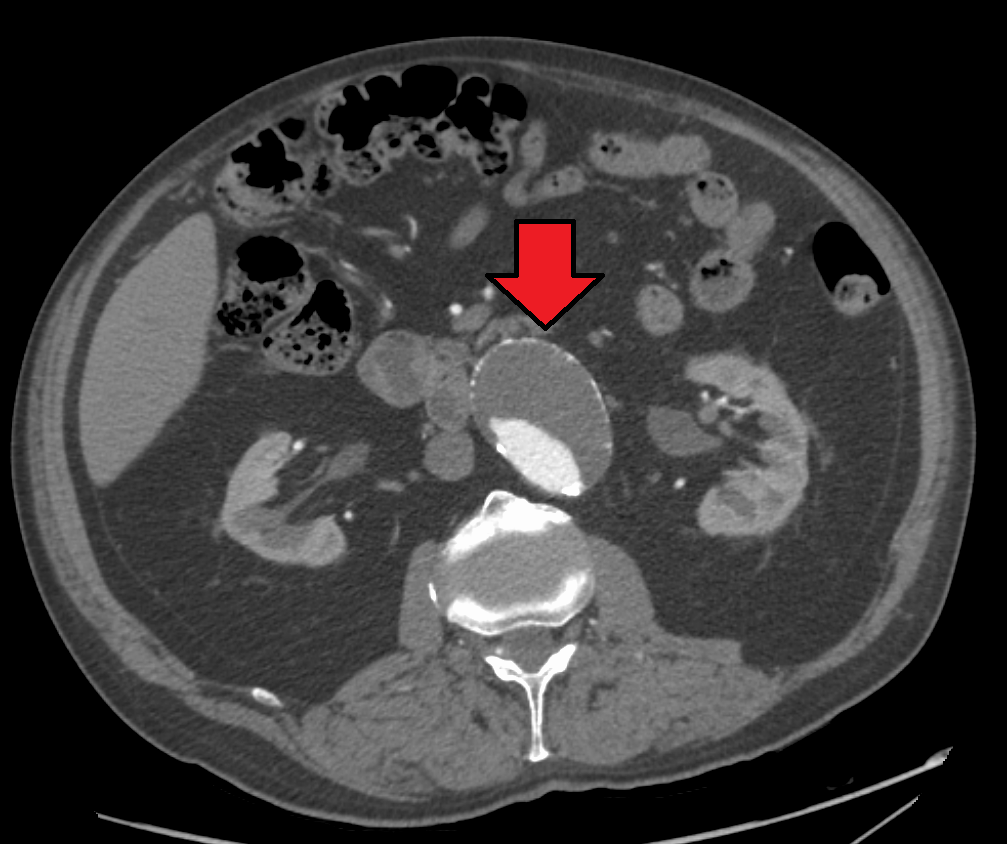

복부대동맥류는 일반적으로 신체 검사, 복부 초음파 검사, CT 스캔으로 진단된다. 단순 복부 방사선 사진은 대동맥벽이 석회화된 경우 대동맥류의 윤곽을 보여줄 수 있지만, 전체 대동맥류의 절반 미만에서만 확인 가능하다.복부 초음파 검사는 대동맥류를 선별하고, 대동맥류가 있는 경우 그 크기를 결정하는 데 사용된다. 또한, 복강 내 자유 액체도 감지할 수 있다. 이는 비침습적이고 민감하지만, 장내 가스나 비만은 유용성을 제한할 수 있다.[29] CT 스캔은 대동맥류에 대해 거의 100%의 민감도를 가지며, 해부학적 구조와 혈관 내 복구 가능성을 상세히 설명하여 수술 전 계획에도 유용하다. 파열이 의심되는 경우, 후복막강 내 체액도 신뢰할 수 있게 감지할 수 있다. 대동맥류를 시각화하는 데 덜 사용되는 대체 방법으로는 MRI와 혈관조영술이 있다.[30]

복부 대동맥류는 일반적으로 신체 검사, 초음파 또는 CT 스캔으로 진단된다. 복부 방사선 사진은 동맥벽이 경화되었을 때 동맥류의 윤곽을 보여주지만, 동맥류 절반 이하에서만 확인 가능하다. 초음파 검사는 동맥류 검사 및 동맥벽 크기 결정에 사용되며, 자유 복막액이 검출될 수 있다. 하지만 장내 가스나 비만은 검출을 어렵게 할 수 있다. CT 스캔은 동맥류에 대해 거의 100% 확신을 가지기 때문에 수술 전 계획에 유용하며, 파열이 의심되는 경우 복막 후방 액체를 확실하게 감지할 수 있다. MRI 및 혈관 조영술도 사용 가능하지만, 자주 사용되지는 않는다.[119]